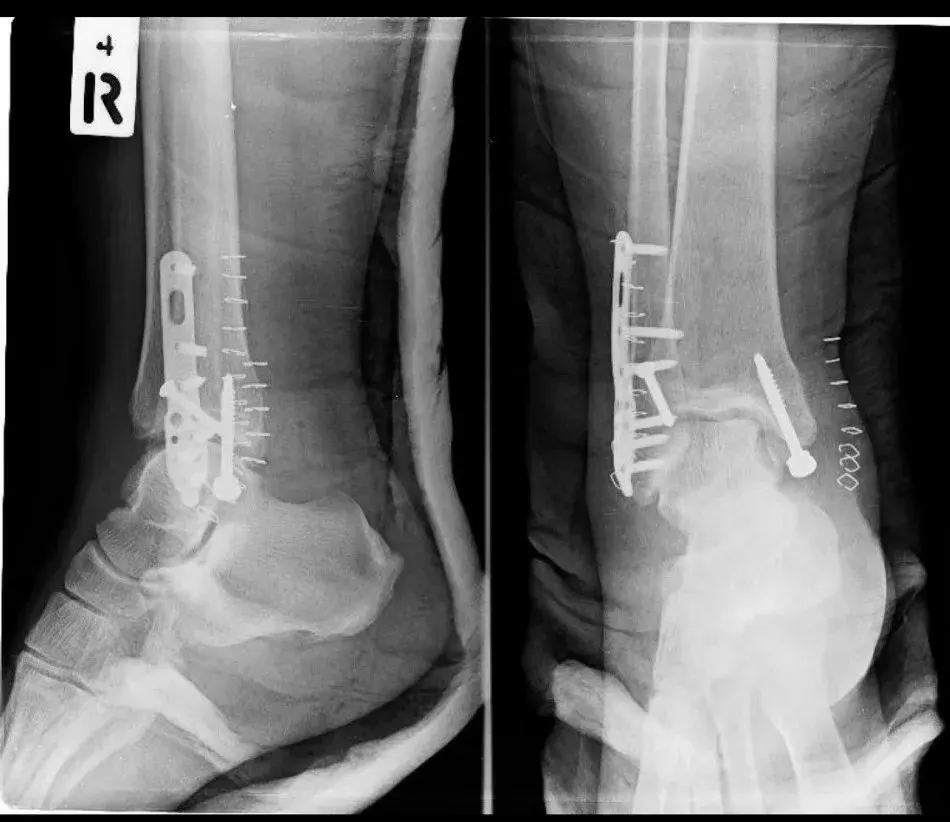

การผ่าตัดใส่เหล็กดามกระดูก หรือที่หลายคนเรียกว่า "ใส่เหล็ก" เป็นวิธีการรักษาเวลาที่กระดูกหักรุนแรง หรือกระดูกหักแล้วไม่สามารถติดกันเองได้ตามปกติ หมอจะใช้เหล็กหรือวัสดุพิเศษมายึดกระดูกให้เข้าที่ เพื่อให้กระดูกเชื่อมติดกันได้เร็วและแข็งแรงขึ้น

เวลาใส่เข้าไป หมอจะผ่าตัดเปิดผิวหนังไปถึงกระดูก แล้วใช้เหล็ก (อาจเป็นแผ่น หรือแท่งยาว ๆ) ยึดกับกระดูกด้วยน็อตหรือตะปูเฉพาะทาง เสร็จแล้วเย็บปิดแผล